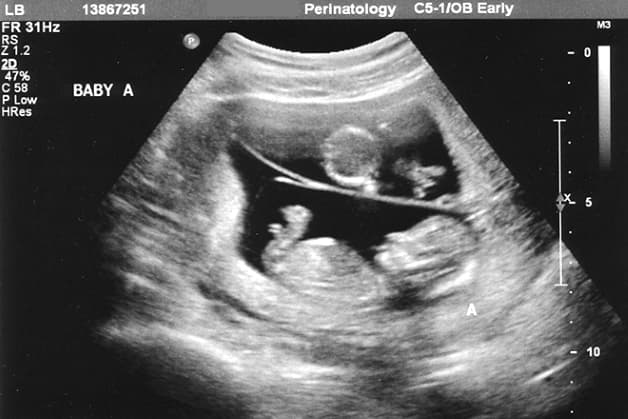

Siêu âm là một trong những phương pháp xác định nguy cơ dị tật bẩm sinh được sử dụng phổ biến nhất hiện nay. Siêu âm có thể giúp phát hiện hầu hết các dị tật về hình thái của thai nhi. Để phát hiện ra được dị tật thai nhi thì bác sĩ sẽ cần phải kết hợp siêu âm với các phương pháp sàng lọc dị tật khác. Có 3 thời điểm siêu âm thai quan trọng giúp phát hiện dị tật bẩm sinh đó là:

Đây là thời điểm siêu âm thai giúp bác sĩ sẽ kiểm tra độ mờ da gáy của thai nhi, thường sẽ được thực hiện từ tuần 11-15 của thai kỳ. Tuy nhiên, thời điểm 12 tuần được xem là mốc kiểm tra mang lại tính chính xác cao nhất.

Đo khoảng mờ da gáy là phương thức tốt nhất để phát hiện sớm các bệnh gây ra bởi nhiễm sắc thể, ví dụ nhự là hội chứng Down. Với kết quả kiểm tra khoảng mờ da gáy, nếu như dày hơn 3mm thì người mẹ phải tiến hành thêm xét nghiệm nước ối để khẳng định lại nguy cơ.

Siêu âm 12 tuần tuổi là giai đoạn giúp bác sĩ đo được khoảng mờ da gáy nhằm phát hiện hội chứng Down